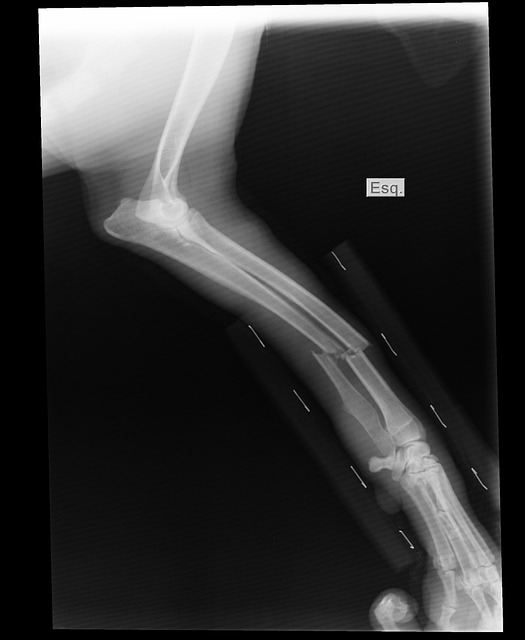

診察室に入ると、先生はレントゲンを指差しました。「ここ、白くなってるところ、折れてるんですよ」と申し訳なさそうに言いました。あー折れてるのか、当分ゴルフ出来ないなと私は落ち込みました。新年からパーソナルレッスンに通い始めて、かなりゴルフに入れ込んでいたところだったからです。

処置室に移ると、私はうつ伏せに寝かされました。そして、骨折した左足の膝から下はあっという間にギブスで固められてしまったのです。